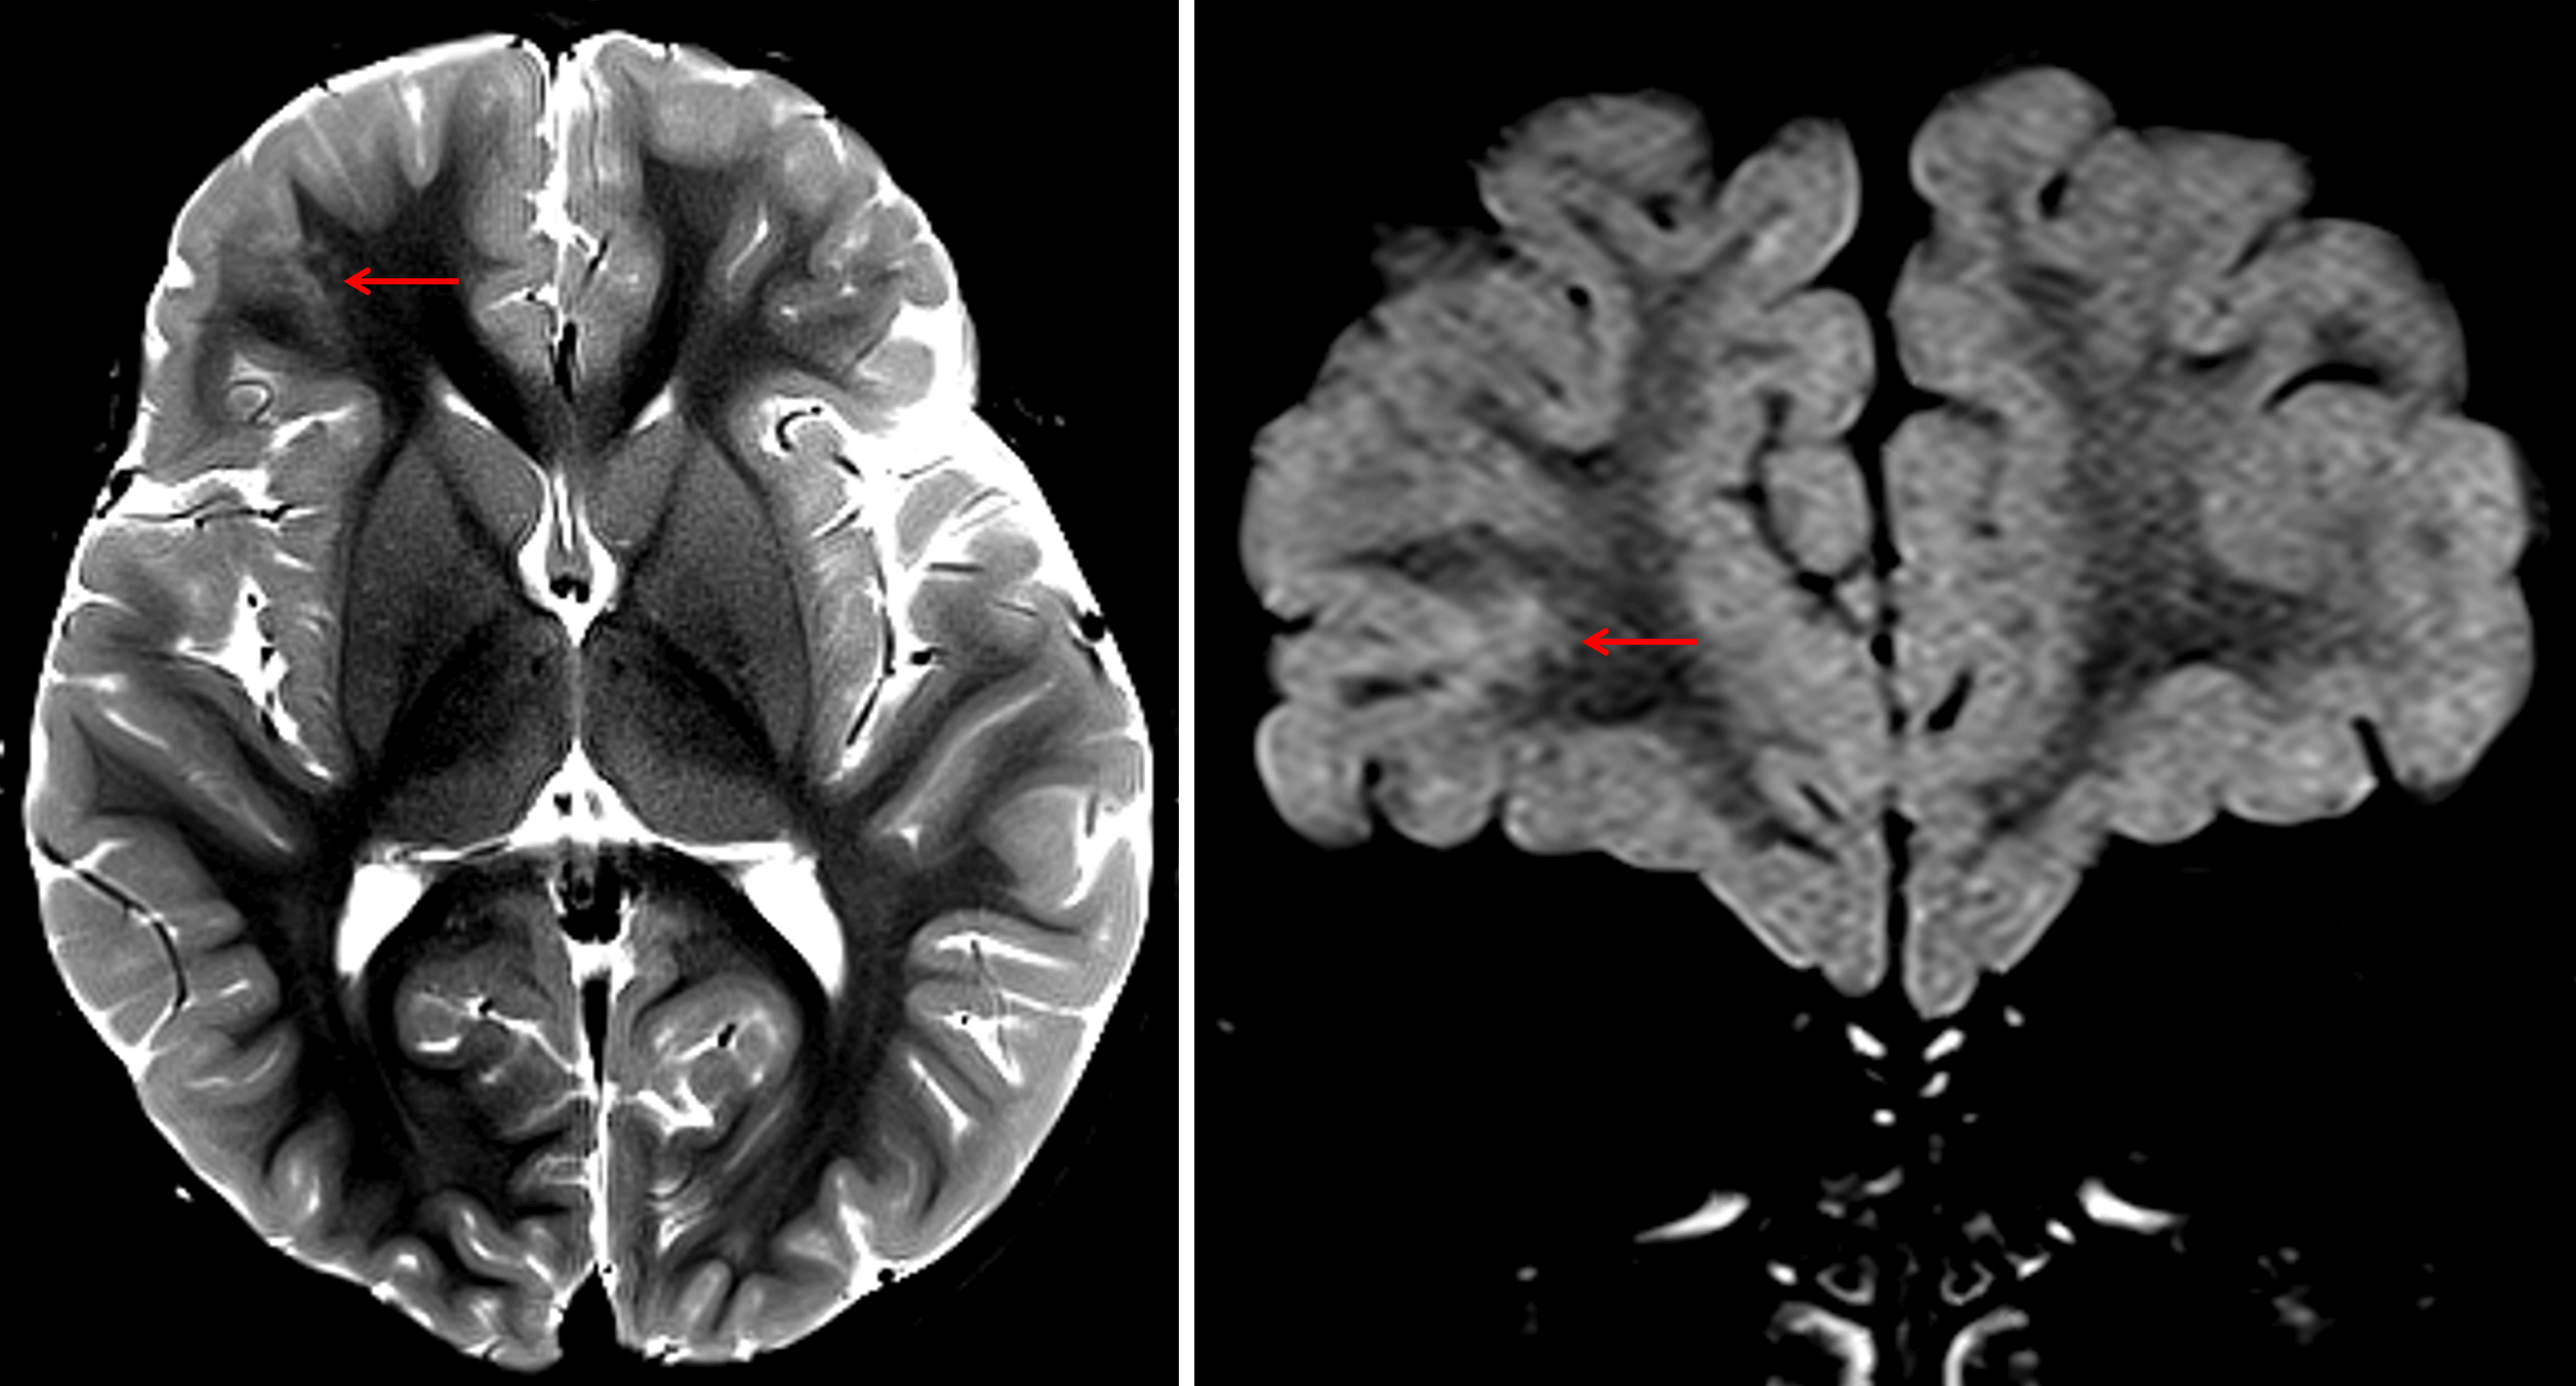

- T2/FLAIR hyperintense lesion in the juxtacortical white matter of the inferior right frontal lobe with likely adjacent cortical involvement

- The lesion has a somewhat multinodular appearance

Nonexpansile T2/FLAIR hyperintense lesion involving the juxtacortical white matter and cortex of the inferior right frontal lobe with a projection of signal hyperintensity extending into the deep white matter (red arrows).

Focal cortical dysplasia VS multinodular and vacuolating neuronal tumor (MVNT)